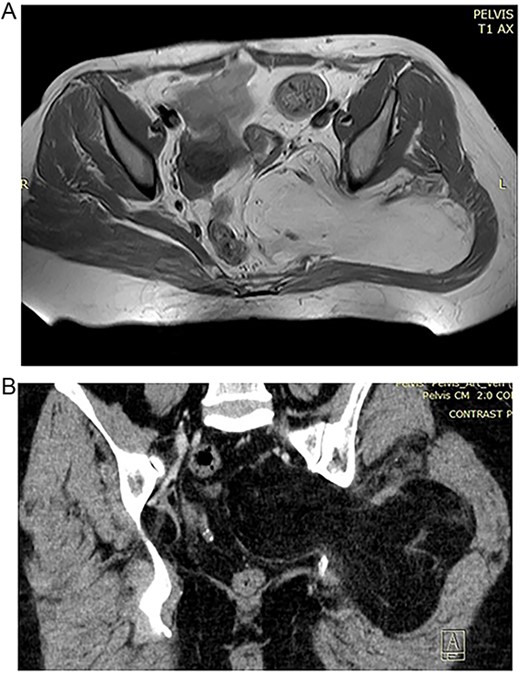

In the 57-year-old female, CT scan revealed a mass inside the pelvis that invades the gluteal musculature (Fig. 1A and B). The mass was homogeneously isointense with fat and ~155×99×148 in size. MRI revealed space-occupying lesions in the right buttock and pelvic cavity, with clear boundaries and smooth edges, not resulting in the displacement of the pelvic organal components.

(A) Preoperative MRT image showing lipoma in the pelvic region. (B) Preoperative CT of the 57 year old patient with high signal of the lipomatous lesion.